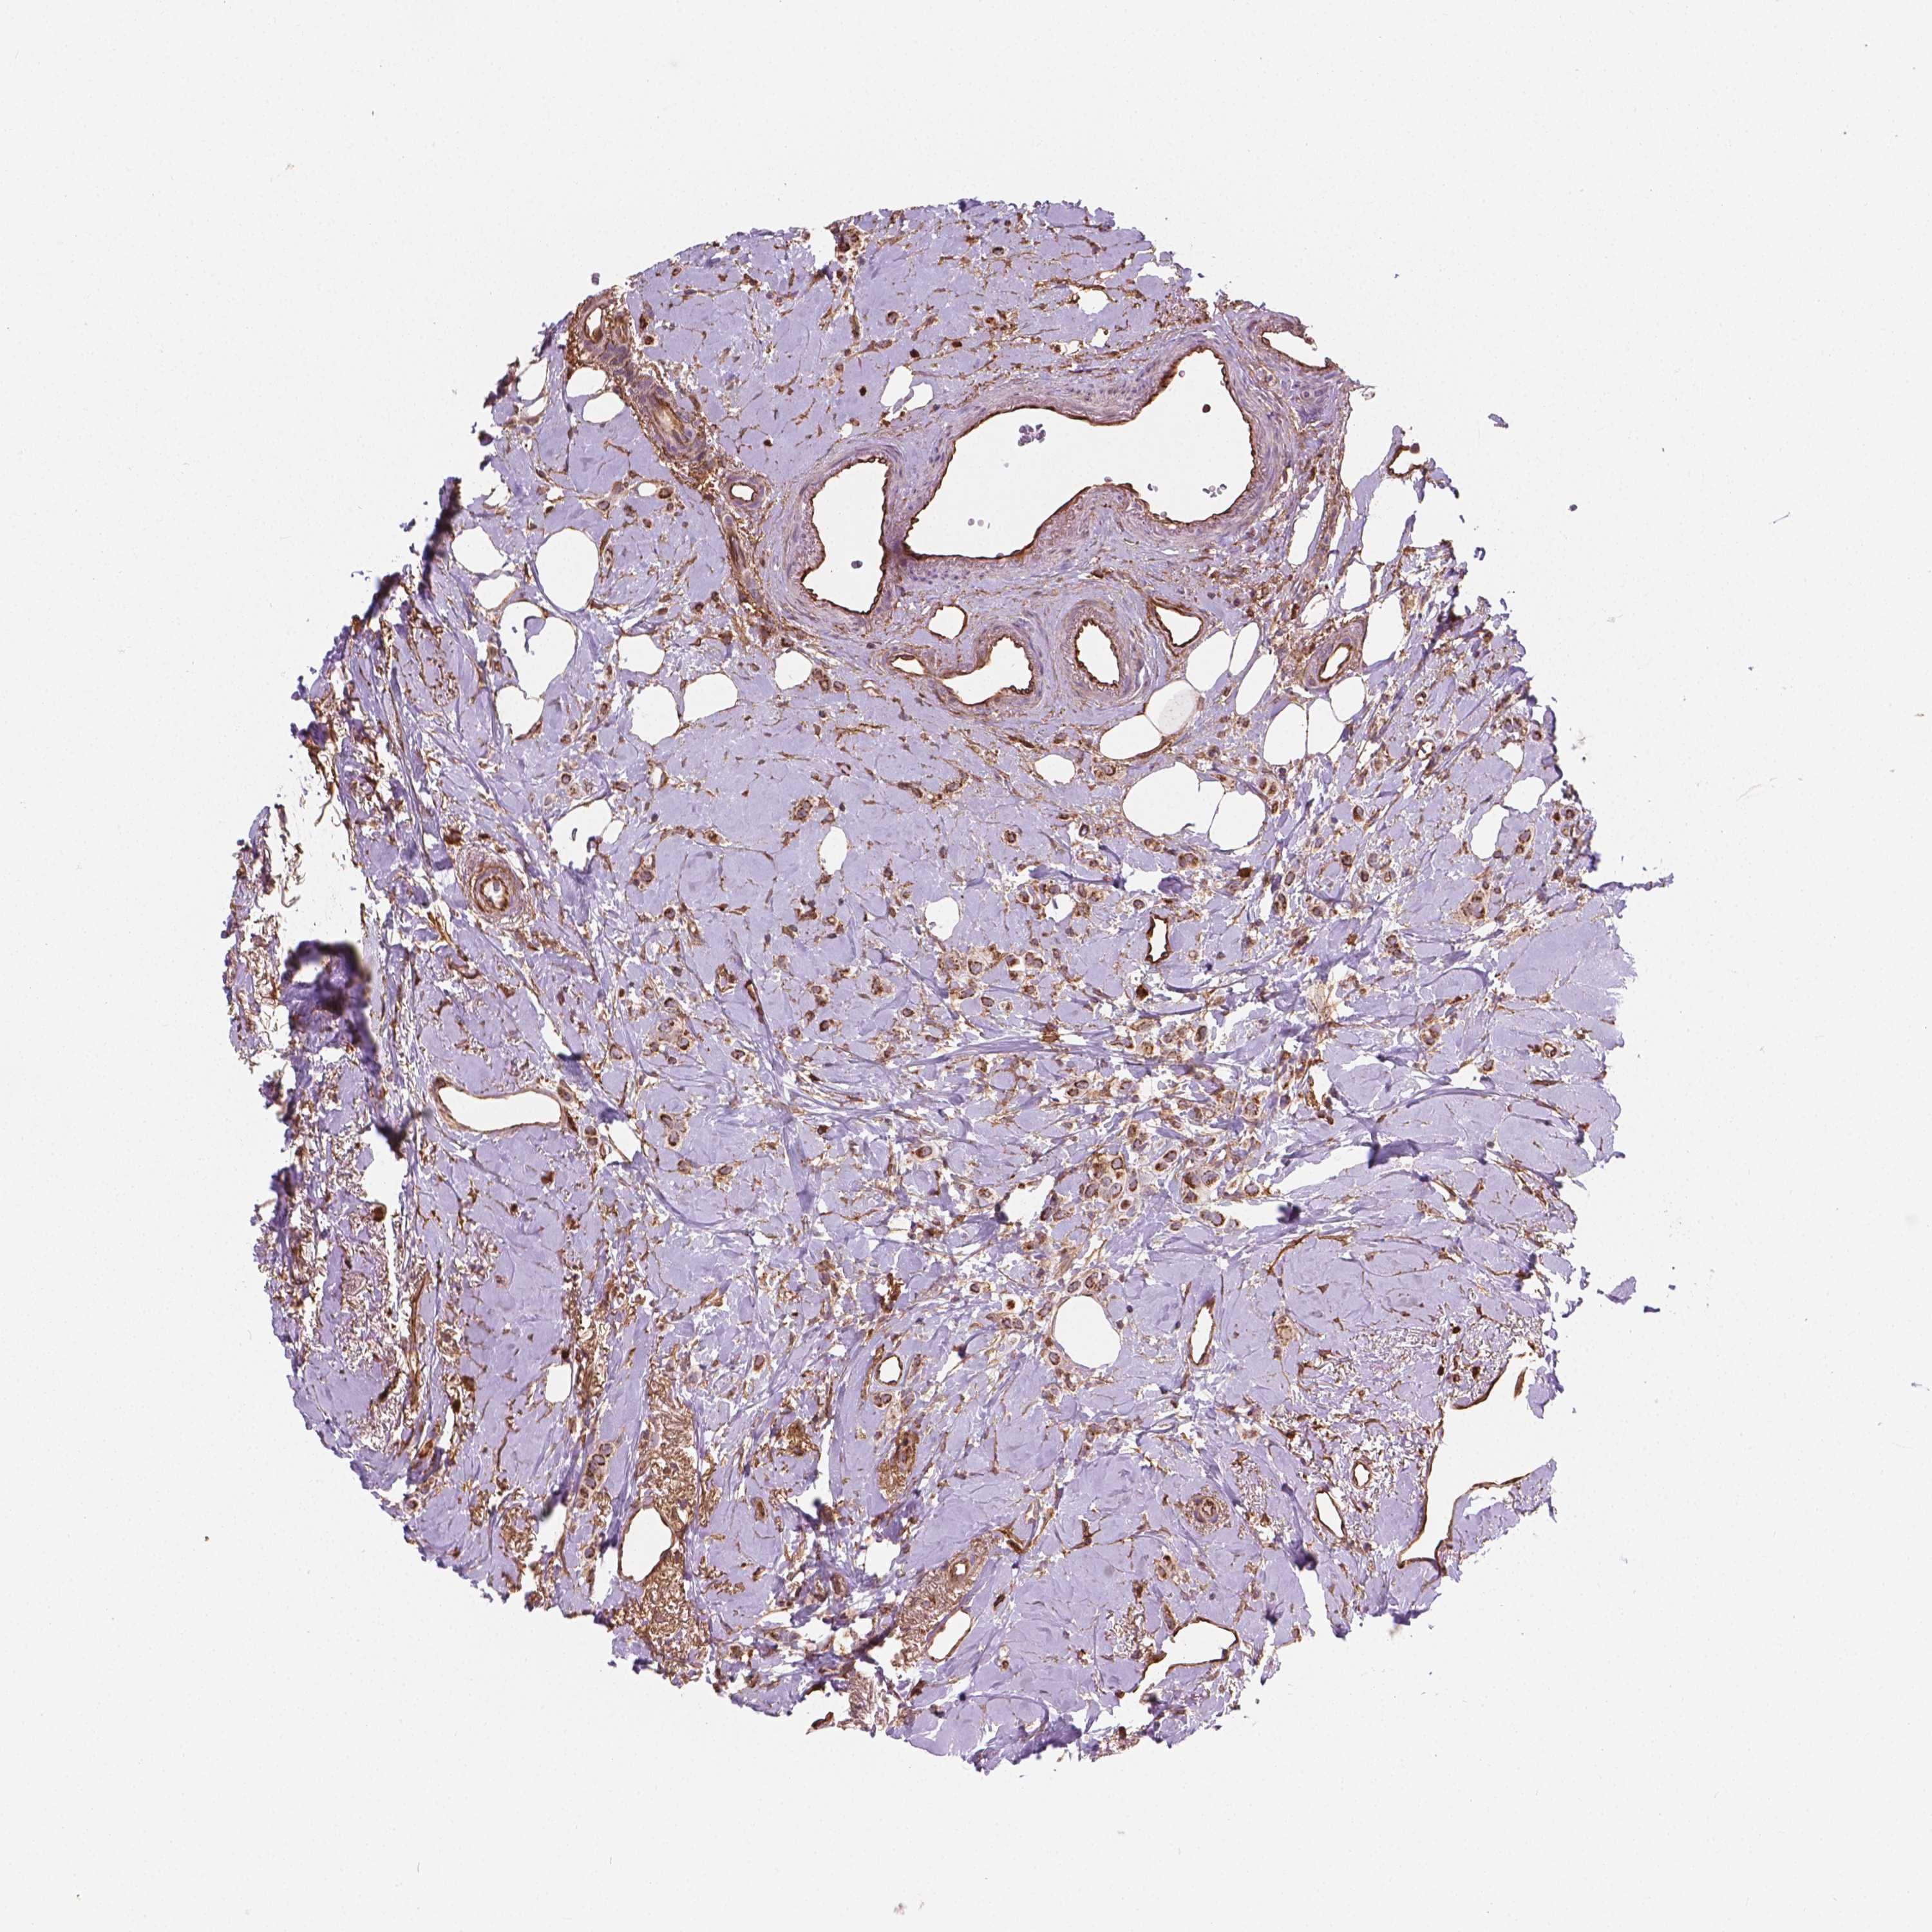

CANCER BREAST CANCER Show tissue menu

Breast cancer

Human cancer

Breast invasive carcinoma